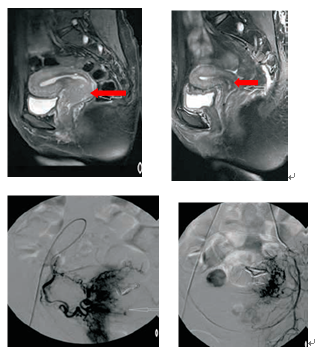

宫颈癌Ⅲb期(巨块型),介入治疗联合放疗后四个月,肿瘤近乎消失

我院妇科现每年收治入院的首诊宫颈癌患者达2000余例,其中相当一部分为晚期及病情复杂患者,在手术、放疗、化疗的“三驾马车”基础上,我院介入科与妇科合作开展宫颈癌双髂内动脉区域灌注化疗术及子宫动脉化疗栓塞术,在近30年的临床实践中积累了数千例的宫颈癌介入化疗经验,目前正在开展碘125粒子组织间内放射治疗和射频及微波消融术,为复发性宫颈癌及晚期妇科肿瘤转移病灶探索新的治疗手段。同时近年来我院介入科在妇科良性肿瘤的介入治疗方面也治疗了许多的患者积累了丰富的经验。